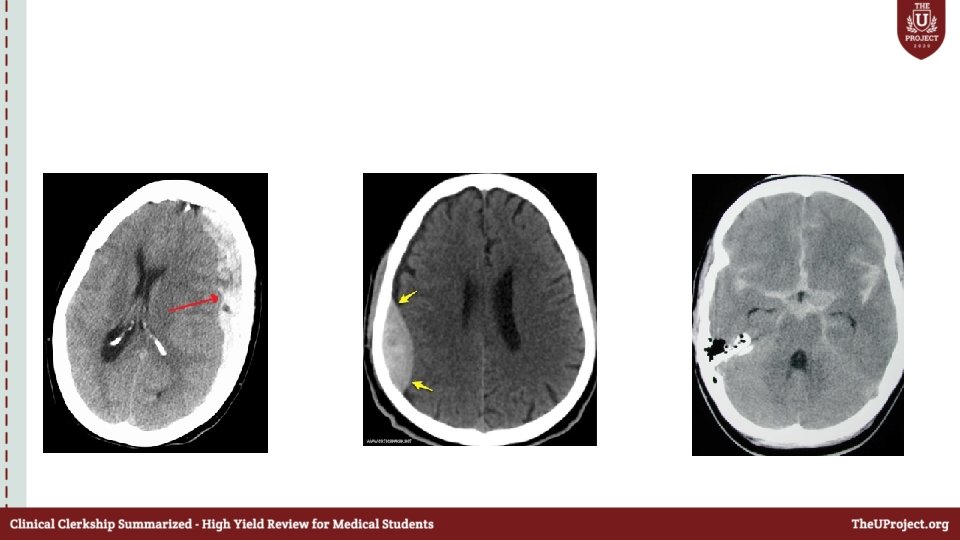

Case 2 • 35 year old male patient was hit by his wife on the head by a metallic pan ; lost consciousness and was brought by EMS to the ED. • As a trauma team leader what will you do before the patient arrives to ED ? • How will you approach this patient ?

Primary survey A: C-spine collar ON Not responding Mouth –full of blood What will you do next ? B: equal air entry bilaterally , SPO 2 100% C: BP 80/60 ; HR 60

• D : GCS: 6 E-1 V-1 M-4 Right pupil was dilated E: No other injuries identified

• What are the signs of raised ICP?

• How will you mainatain the cerbral perfusion pressure ?